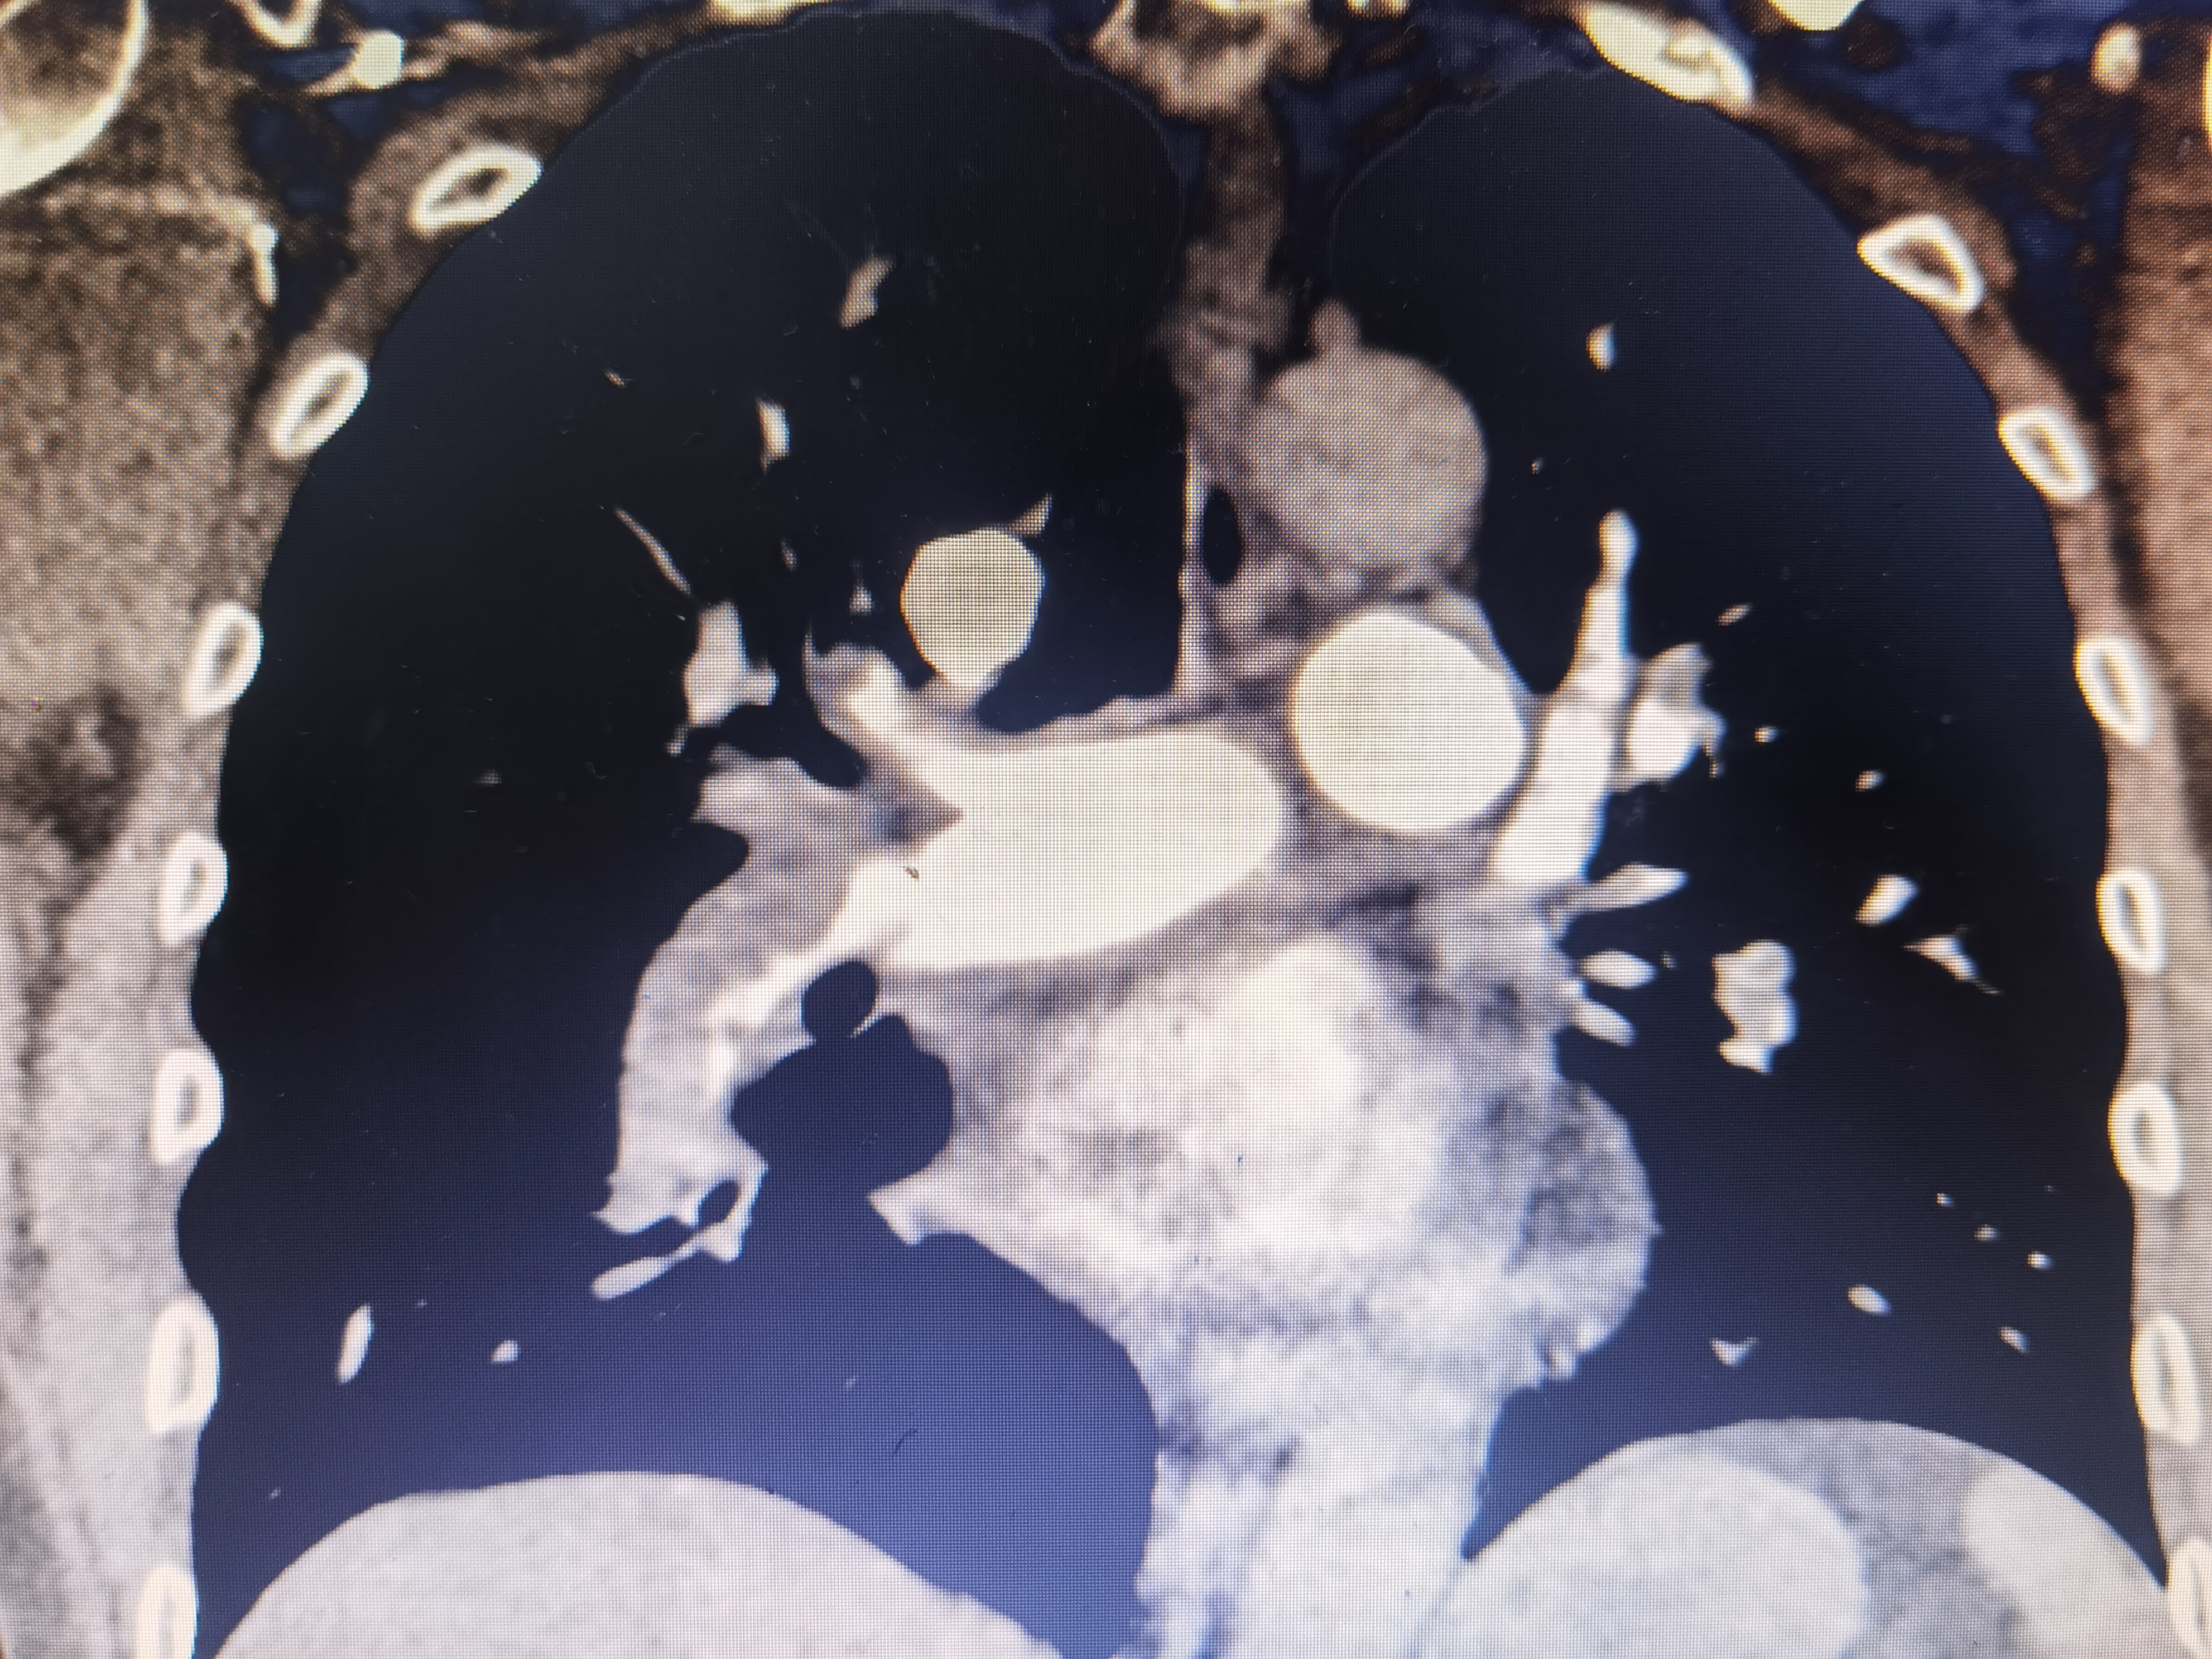

CTA顯示的肺動脈血栓 CTA顯示的肺動脈血栓 CTA顯示的肺動脈血栓 DSA血管介入下取血栓,局麻微創(chuàng) 吸栓導(dǎo)管吸栓 取出的血栓,患者立即感呼吸輕松多了